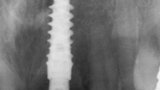

Fig. 3: Pre-op periapical radiograph.

Fig. 4: Pre-op CBCT scan.